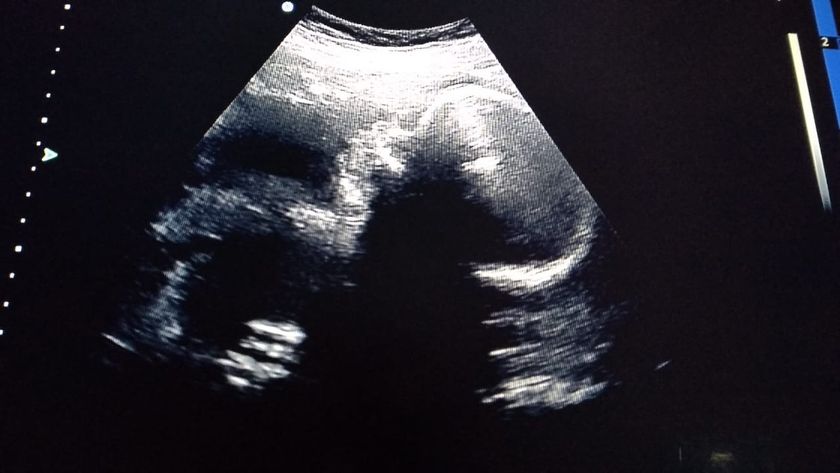

Всем привет! Как у вас дела? Вчера сходила на скрининг. Конечно чуточку расстроилась. Пдр на 22го февраля по месячным по первому ставили с 22-25 февраля а сейчас поставили на 4 марта. Сказала что вес маленький из за этого. Сегодня 30 недель 2 дня а по третьему скринингу 28,4. У кого такой вес был? Я себя настраиваю что мы миниатюрные. А по остальному все в норме. Сыночек ручкой мне махал.

Хорошенький.Все хорошо у вас, просто не крупный

Ой, какой лапатуша! Конечно малютки! Все будет хорошо!